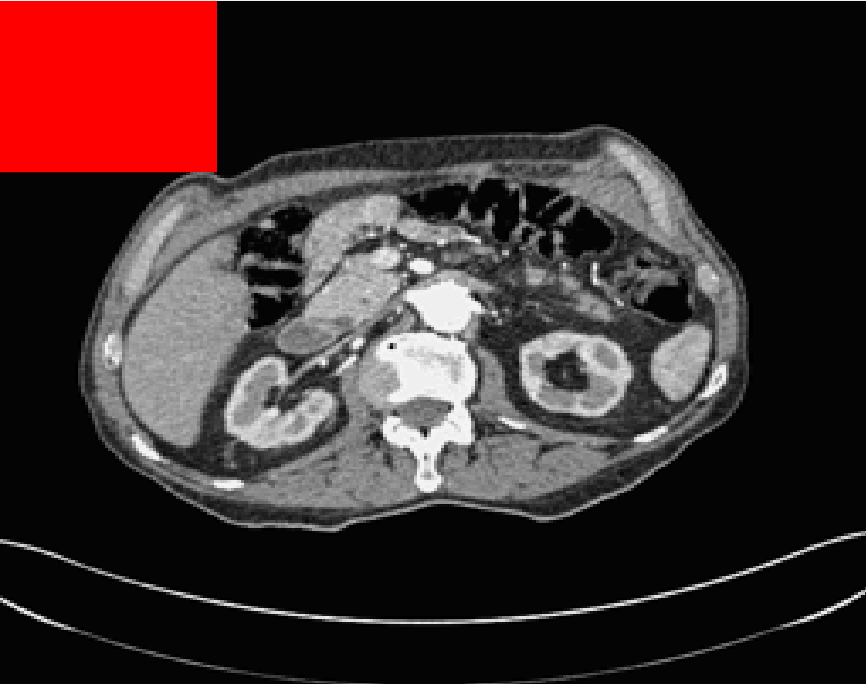

Test Images. We will perform initial tests on the images shown in Figs. 5–7. We have provided the ground truth and initialisation used for each image. Test Images 1–3 are synthetic, Test Image 4 is an MRI scan of a knee, Test Images 5–6 are abdominal CT scans, and Test Images 7–9 are lung CT scans. They have been selected to present challenges relevant to the discussion in §2. We focus on medical images as this is the application of most interest to our work. In the following we will discuss the results in terms of synthetic images (1–3) and real images (4–9). We also test the proposed approach on a larger data set of 30 CT images (a sample of which is presented in Fig. 18), comparing against existing selective methods detailed in §3.

Real Images. In Fig 12 we present results for Test Images 4–6. Here, the proposed model performs in a similar way to its competitors because these images are more typical selective segmentation problems in the sense that there is a clear distinction between the foreground and background intensities. In particular, the values in each case are: Test Image 4 , Test Image 5 , and Test Image 6 . It can be seen that the proposed model is competitive compared to previous approaches. The performance is quite poor for Test Image 5, but is arguably still the best for this challenging case. In Fig. 13 we present results for Test Images 7–9. Here the proposed model outperforms previous approaches significantly for each image. This is mainly due to the type of image considered. Specifically, the true intensities are: Test Image 7 , Test Image 8 , and Test Image 9 . The proposed model is capable of achieving results where , with other models failing completely in these cases.